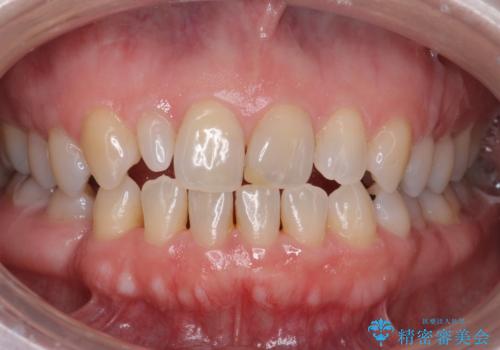

また、向かい合う上の歯が挺出(伸び出してしまうこと)しており、インプラントを入れることが難しかったため、長さを短くかぶせ治しました。

また、上顎前歯以外の根の治療のやり直しを行いました。

上顎前歯は他院で根管治療とセラミックを行なったとのことで、歯肉縁下形成のため、歯肉の腫れが治りにくい状況でしたがやり直しは希望されませんでした。